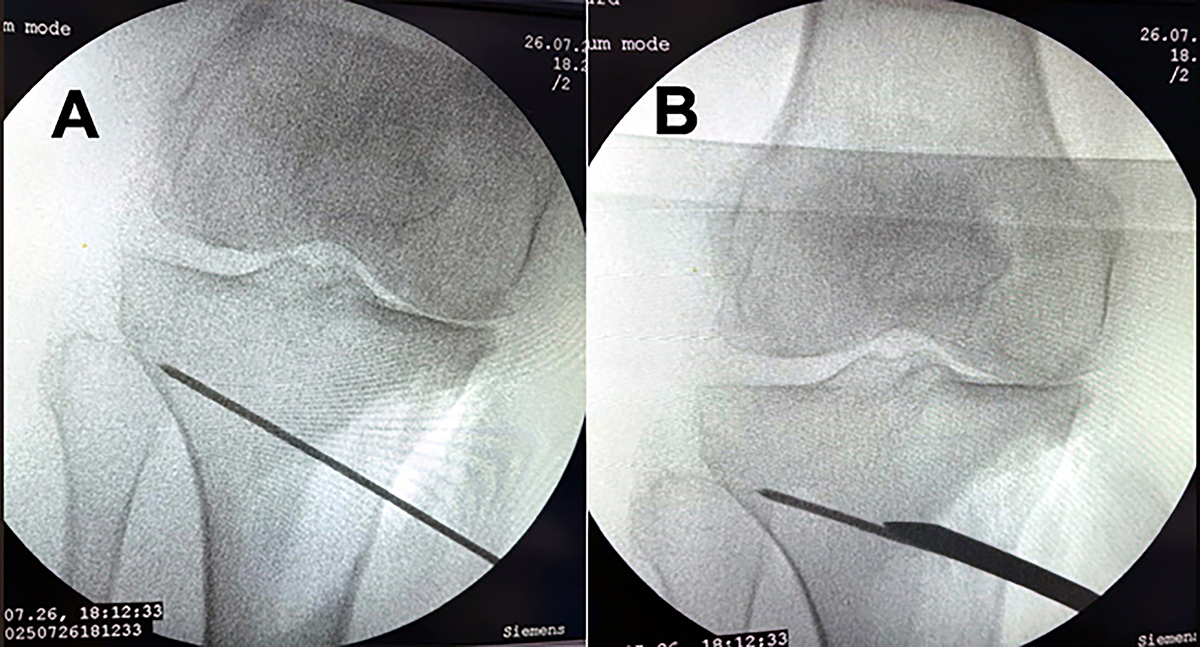

An intraoperative fluoroscopy picture; (A) A K-wire was inserted into the medial surface of the proximal tibia directed towards tip of the fibular head. (B) An osteotome was used to cut the bone in the direction of K-wire.